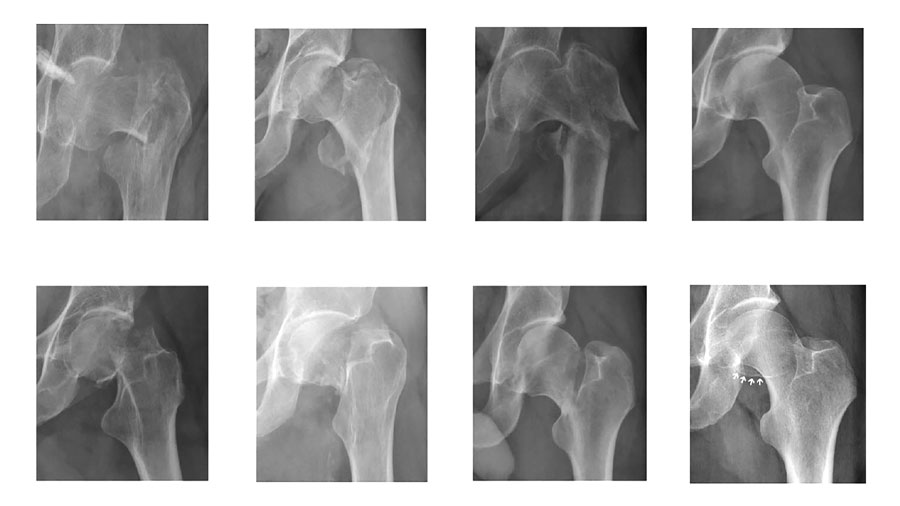

A recently completed collaboration between the AO Foundation and the University of Turin, published in Injury as a proof‑of‑concept (PoC) study and supported AO Innovation Funding, addresses this challenge by validating the “ground truth” of a large radiographic image database of proximal femur fractures.

The study assessed how consistently expert surgeons classify fractures on standard anteroposterior radiographs using the AO/OTA system, and whether these annotations are robust enough to support future AI development.

Two independent groups of expert surgeons—one from the AO Foundation and one from the University of Turin—reviewed and classified the same set of 300 radiographs. Overall agreement was high, confirming that expert‑based annotations can be reliable when a structured workflow is applied. Where disagreements occurred, they were not random but clustered around specific fracture boundaries, particularly between AO/OTA 31A1 and 31A2 fractures, and between “no fracture” and 31B fracture.